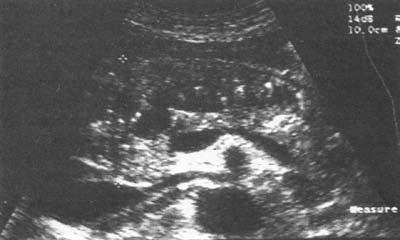

Ультразвуковое исследование (сканирование) является одним из наиболее информативных и притом неинвазивных методов исследования ПЖ и должно осуществляться во всех случаях, когда подозревается ее патология (рис. 137–139).

Датчик располагается в эпигастральной области и его перемещают соответственно проекции железы на области левого и правого подреберий. В норме ПЖ имеет ровные, четкие контуры и гомогенную структуру, а диаметр главного панкреатического протока не превышает 1,5–2 мм. При патологии может выявляться общее увеличение размеров органа с равномерным уменьшением эхоплотности, свидетельствующее об отеке. Уменьшение размеров железы, неоднородность структуры, наличие мелких участков уплотнения ткани, а также нечеткость контуров могут говорить о фиброзных изменениях в железе, а небольшие резко выраженные эхоположительные узелки – об очаговом обызвествлении паренхимы. Эхоструктуры высокой плотности, расположенные в протоке и дающие феномен «ультразвуковой дорожки», являются признаком внутрипротоковых конкрементов. Жидкостные образования (ложные кисты, вялотекущие абсцессы) представляются на эхограмме округлыми участками значительно пониженной эхоплотности с более или менее четкими контурами и дорсальным усилением. Хорошо сформированные ложные кисты с жидким содержимым имеют округлую или овальную форму, гомогенны и окружены четко выраженной капсулой. Содержимое несформировавшихся кист и абсцессов может быть неоднородным из‑за наличия в них, помимо жидкости, тканевых секвестров и детрита.

Рис. 138. Хронический кальцифицирующий (калькулезный) панкреатит.

Кальцинаты в паренхиме ПЖ